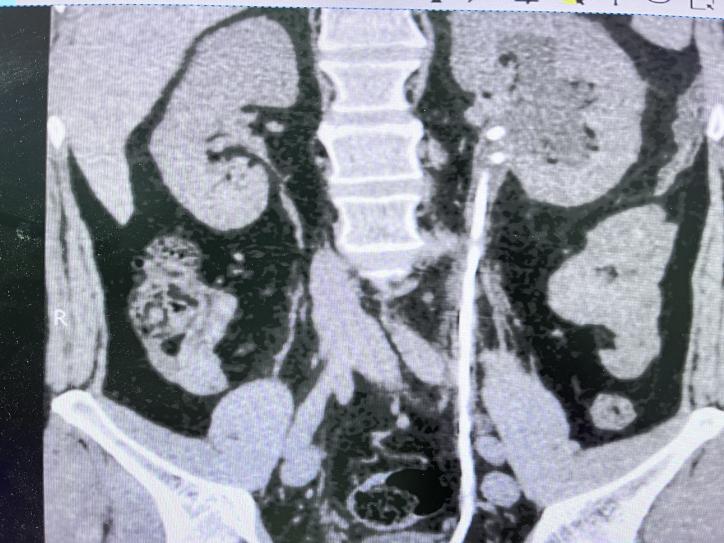

术后1个月复查CT如下: